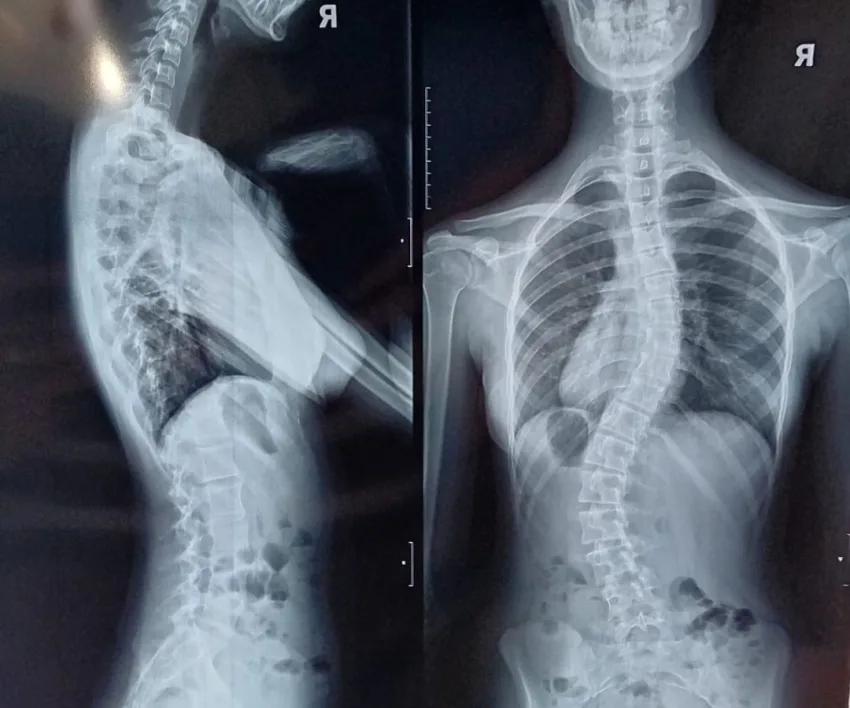

Erika Maria Stingaciu este o adolescentă de 15 ani care se confruntă cu un diagnostic sever de scolioză dorsolombară progresivă, o afecțiune care îi modifică zilnic postura și îi afectează profund calitatea vieții. Până în urmă cu doi ani, Erika era un copil obișnuit, cu planuri simple și o copilărie trăită firesc. Totul s-a schimbat…